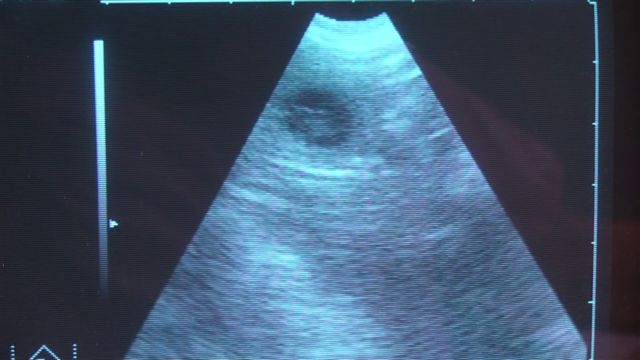

妊娠診断 超音波検査

妊娠22日目 羊水が1cmくらいの球状で確認できる

膀胱以外の水がたまっているところを探す。この犬は3個以上確認できた。エコーでの妊娠診断は30日以降で行う